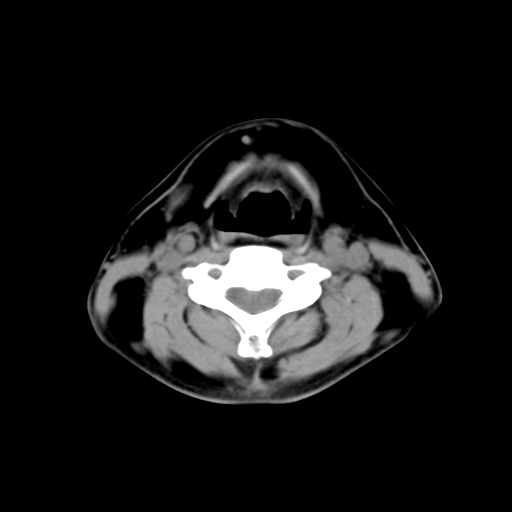

标题: CT24019:男,45岁,发现颈部肿物5个月。 [打印本页]

男,45岁,发现颈部肿物5个月,彩超示:双侧颈部及下颌部软组织增厚。

考虑双侧颈项部良性对称性脂肪增多症。